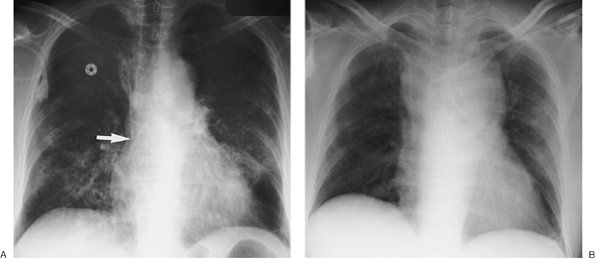

FIGURE 5-12. Pulmonary artery pseudoaneurysm as a complication of pulmonary artery catheter placement. A: AP chest radiograph shows pulmonary edema and the tip of a pulmonary artery catheter projected over an expected left lower lobe segmental pulmonary artery branch (arrow). B: The distal placement of the catheter tip resulted in perforation of a subsegmental pulmonary artery and development of a pulmonary artery pseudoaneurysm, shown as an enhancing mass in the left lower lobe on CT (arrow).